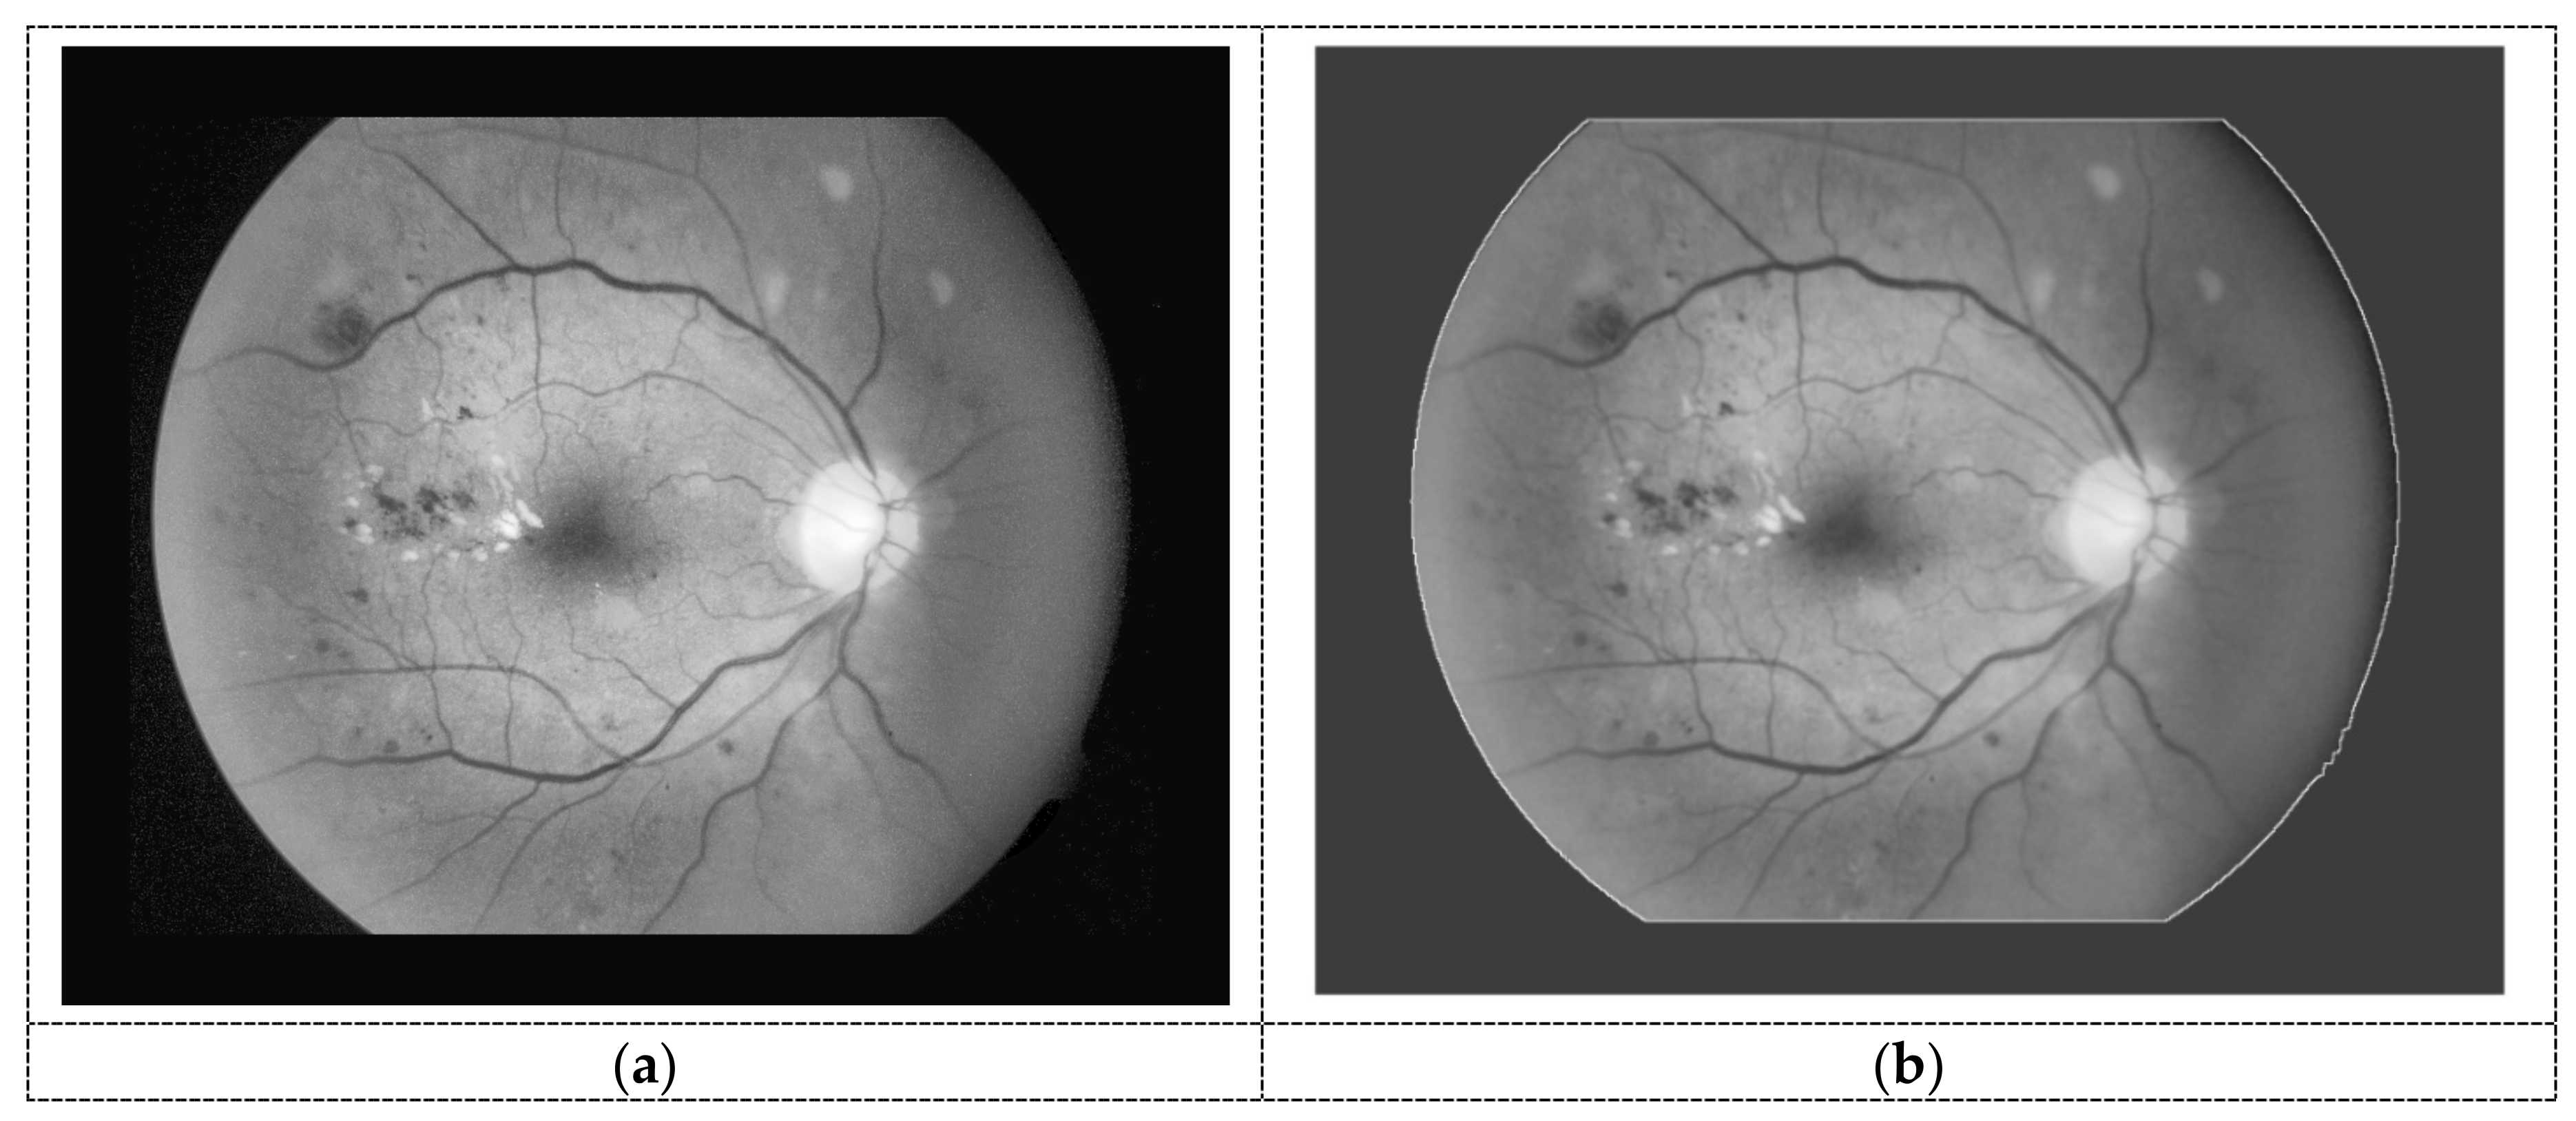

2.2.1. Preprocessing Stage

Brightness and Contrast Enhancement

3.3. Preprocessing Result